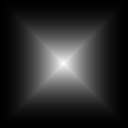

As a trade-off of these issues, we designed a weighted loss and a scheme for patch extraction and assembling to allow the neural network to predict an segmentation map of equal size without concerning the lack of context issue in the border area.

where Wi,jsubscript𝑊𝑖𝑗W_{i,j} is the weight of position i, j, , Di,jesuperscriptsubscript𝐷𝑖𝑗𝑒D_{i,j}^{e} is the distance from border, Di,jcsuperscriptsubscript𝐷𝑖𝑗𝑐D_{i,j}^{c} denotes the distance from center.hh and w𝑤w are the height and width of the map, respectively.

Refer to caption

Figure 5: The weighted loss map generated by Eq.3

III-C2 Nuclei Segmentation on Extra-large Images

To evaluate the effectiveness of the proposed weight map and overlapped patch extraction and assembling method for extra-large image segmentation, we compared the segmentation results with and without the proposed method in Fig. 11. We can see that the raw segmentation results without using those two techniques contain obvious seams between the patches. It also demonstrates that the predictions in the border area is not accurate. As shown in Fig. 11(d), if we employ the overlapped patch extraction and assembling but without the weight map (which means all the pixels in a patch have the same weight) the segmentation result still shows noticeable seams. Fig.11(b) and Fig. 11(d) has the same stride, which is 64.